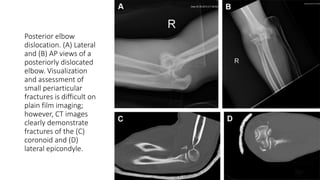

Posterior elbow

dislocation. (A) Lateral

and (B) AP views of a

posteriorly dislocated

elbow. Visualization

and assessment of

small periarticular

fractures is difficult on

plain film imaging;

however, CT images

clearly demonstrate

fractures of the (C)

coronoid and (D)

lateral epicondyle.

Posterior elbow dislocation. (A)Lateral and (B) AP views of a posteriorly dislocated elbow. Visualization and assessment of small periarticular fractures is difficult on plain film imaging; however, CT images clearly demonstrate fractures of the (C) coronoid and (D) lateral epicondyle.